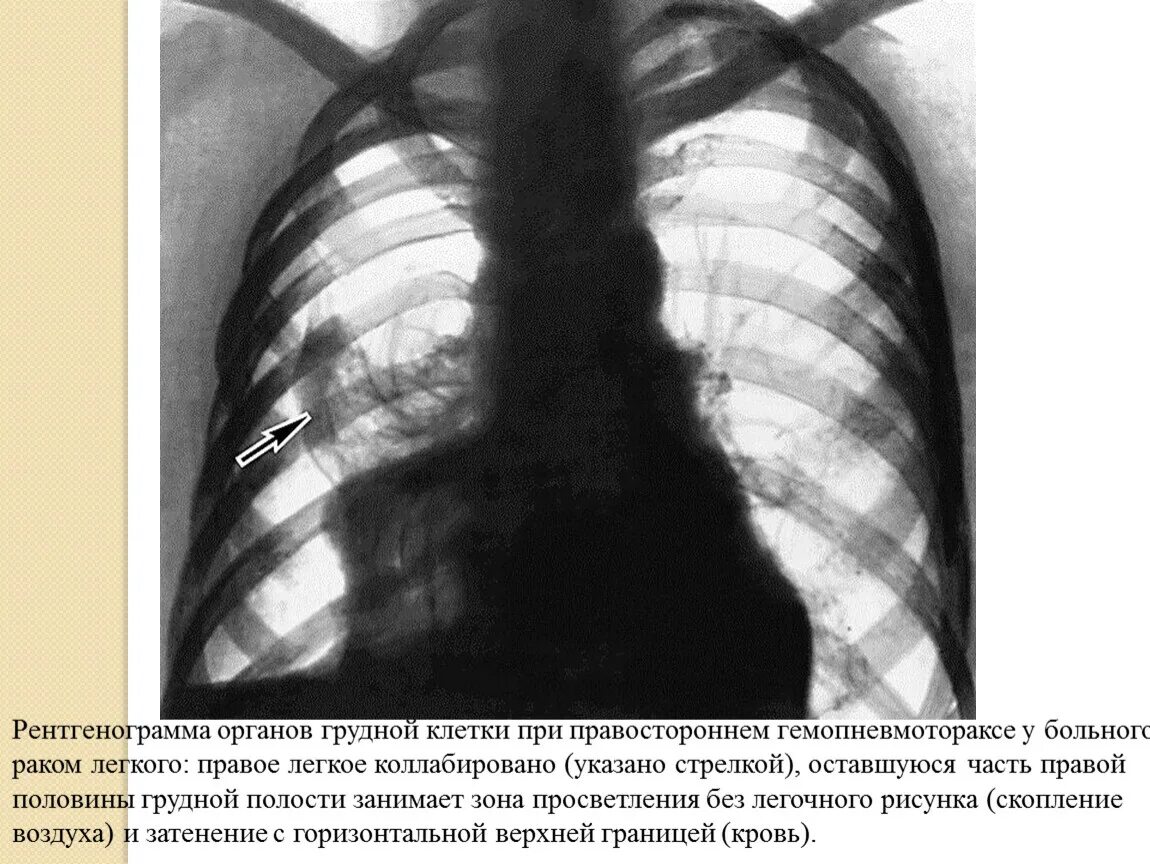

Покалывание в легких